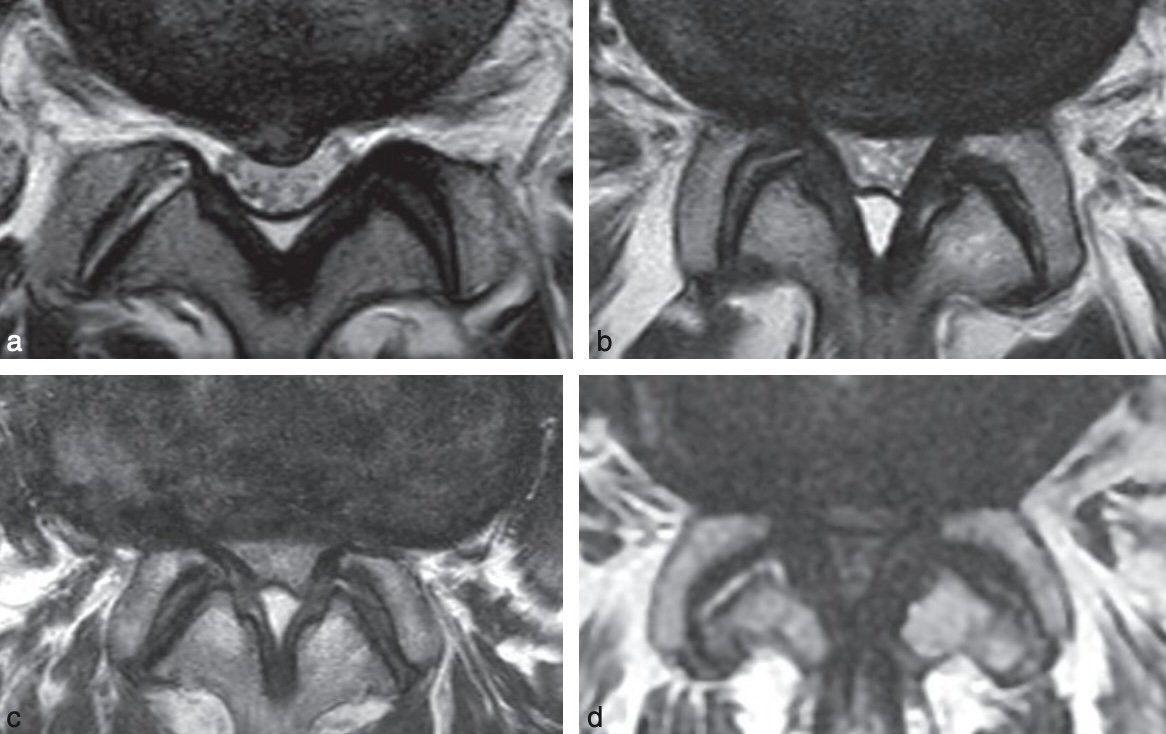

Schizas A sténose minime : LCS visible, B modérée : peu visible,

C sévère : ∅ LCS, D extrême : ∅ graisse épidurale